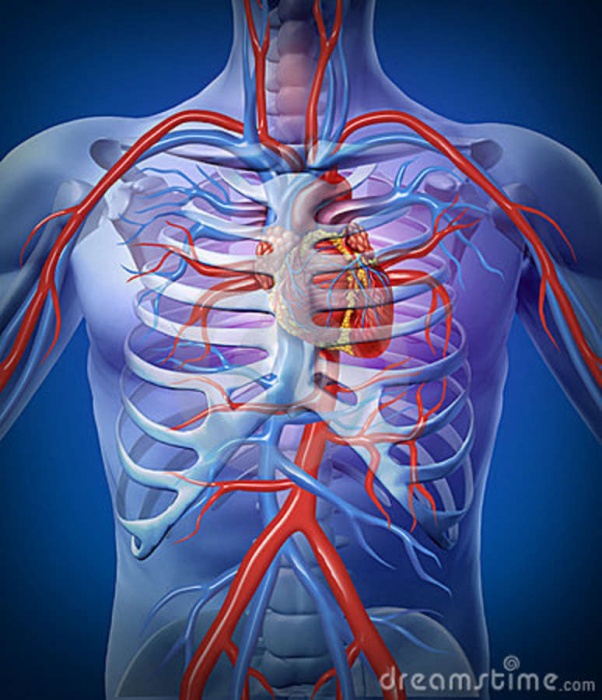

استقامت قلبی تنفسی

استقامت قلبی تنفسی نشان می دهد که بدن چقدر می تواند سوخت را در طول فعالیت بدنی از طریق سیستم گردش خون و تنفس بدن تامین کند.

فعالیتهای هوازی که به بهبود استقامت قلبی تنفسی کمک میکنند، فعالیتهایی هستند که باعث افزایش ضربان قلب برای مدت زمان طولانی میشوند.

به عنوان مثال شنا، پیاده روی سریع، دویدن، دوچرخه سواری.

ارتباط استقامت قلبی تنفسی با کمردرد

ورزش هوازی جریان خون و مواد مغذی را به بافتهای نرم، از جمله بافتهای کمر و پشت، افزایش میدهد و روند بهبودی را تسریع میکند .

سی دقیقه ورزش هوازی باعث افزایش تولید اندورفین در بدن می شود که یک جایگزین طبیعی برای تسکین درد برای بدن است.

این به سطوح درد مراجعین کمک می کند و ممکن است اتکا به دارو برای درد را کاهش دهد.

سطح پایین تناسب اندام هوازی با کمردرد مزمن مرتبط است